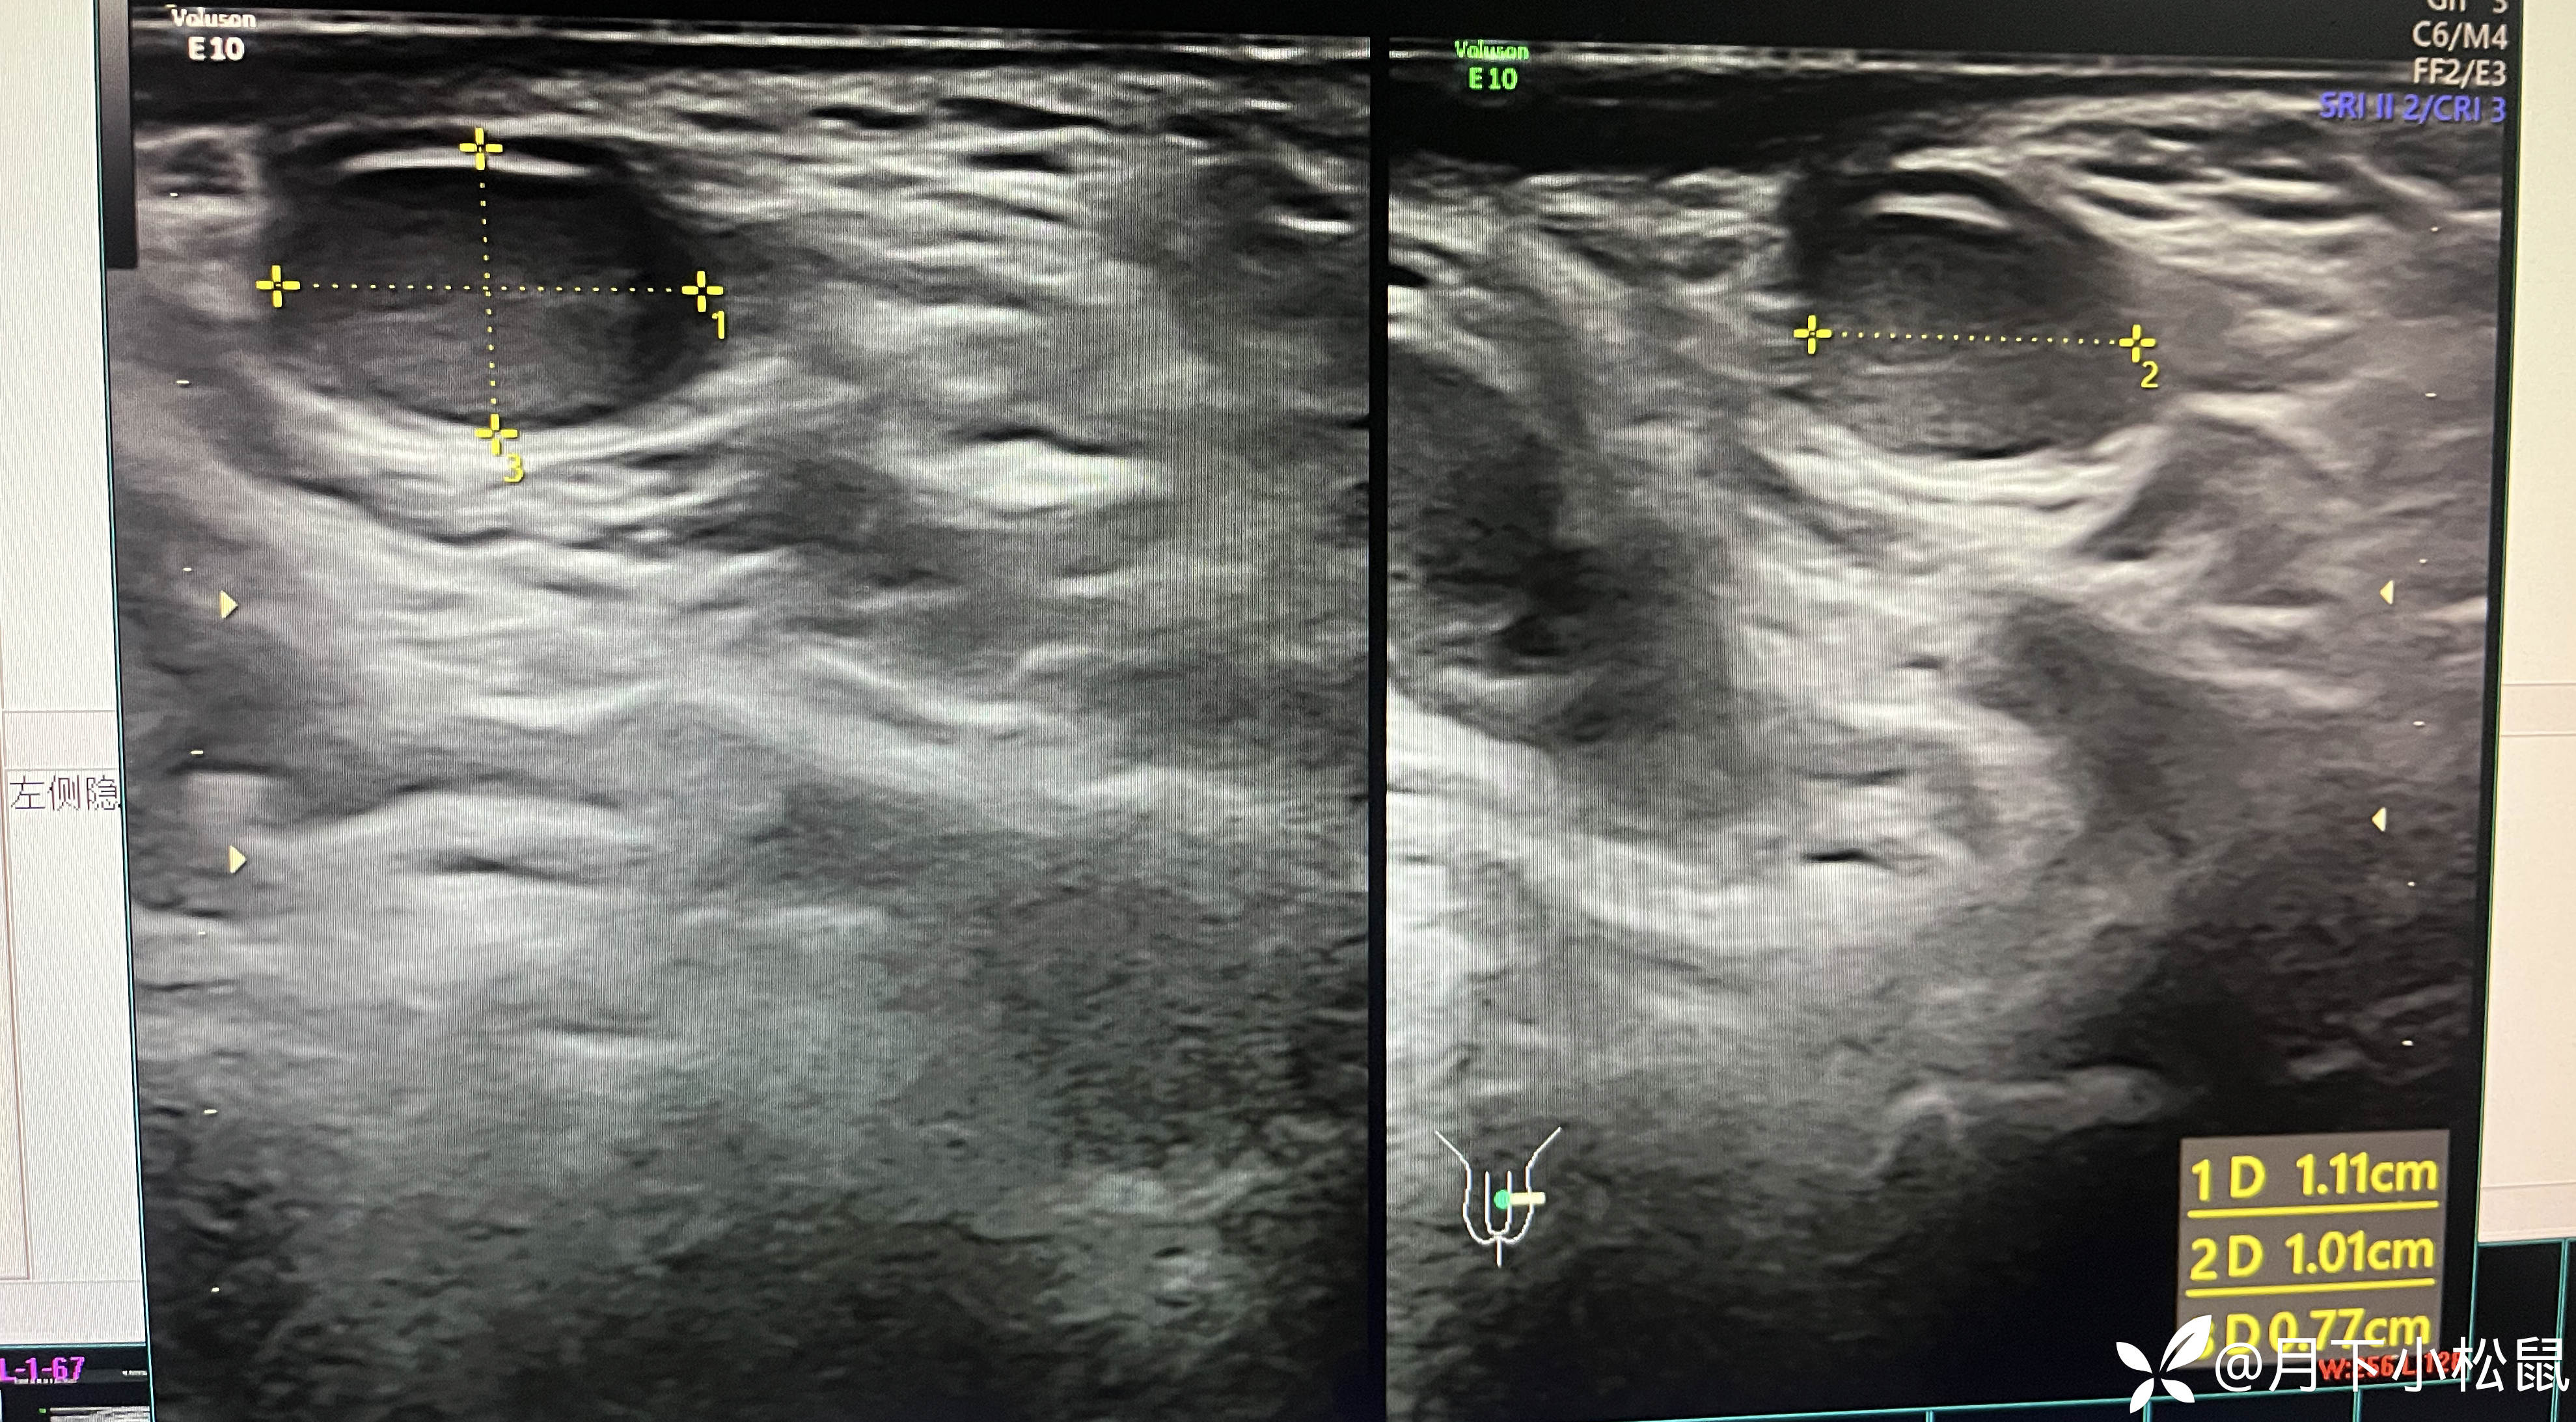

给开了B超,申请单上面写了详细的体格检查内容,同时嘱家属在做B超时一定和做B超的医生说仔细看看蛋蛋。

腹部B超检查报告回报示:

报告: